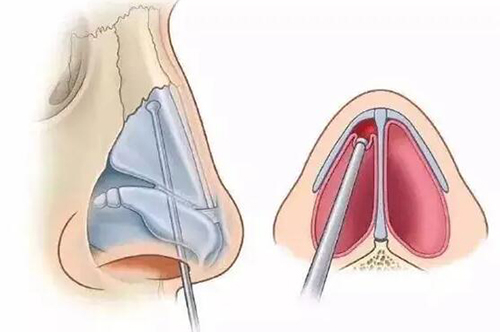

杭州做鼻子大概多少钱?2025注射隆鼻3000元起、假体隆鼻8000元起、膨体隆鼻1万元起!

杭州做鼻子大概多少钱?2025注射隆鼻3000元起、假体隆鼻8000元起、膨体隆鼻1万元起!在杭州,做鼻整形的价格跨度较大,从3000元的玻尿酸注射到12万元的复杂鼻修复手术均有覆盖。价格差异主要由手术方式、材料选择、医生技术及机构定位共同决定。本文结合2025年杭州多家显

杭州注射隆鼻医院哪个好?文中六家正规靠谱机构一定要知道,这几家注射都有出色口碑~

杭州注射隆鼻医院哪个好?文中六家正规靠谱机构一定要知道,这几家注射都有出色口碑~杭州注射隆鼻医院哪个好?一句话先给答案:想打鼻子又不敢开刀,直接去「浮想国」「艺星」「天鑫」「维多利亚」「星光丽格」「浙江杭州整形医院」这六家就够挑了,全是杭州本地小姐姐